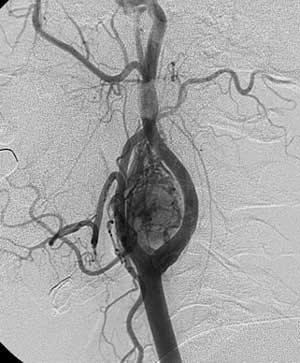

Рис. 1. В области бифуркации левой общей сонной артерии определяется гиперваскулярная опухоль с девиацией сонных артерий - каротидная параганглиома.